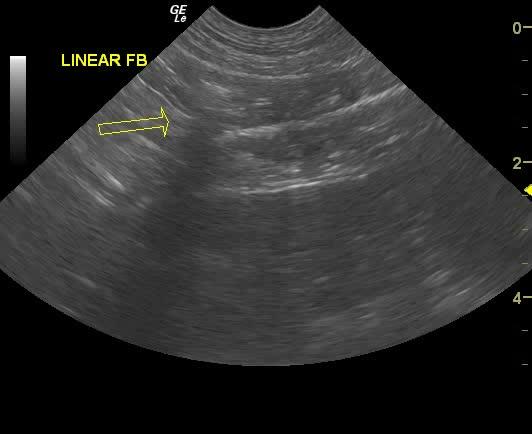

The stomach presented with a 5.0 cm linear foreign body that continued into the duodenum and small intestine. Accordion pleating was noted in the distal small intestine as well as ileocecal region.

Gastric, duodenal ileocecal foreign body. Immediate exploratory is recommended.